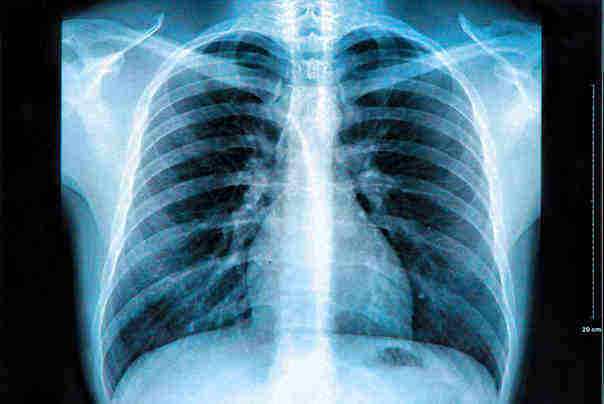

Nakon nekoliko dana naročito jakog kašlja, Ksiao je doživela je jaku bol u levoj strani grudi,.Na kraju su doktori otkrili da je kašalj prouzrokovao 10 slomljenih rebara

Lekari su potom obavili više testova koji su otkrili da ima mlada Ksiao i značajno nižu gustinu kostiju od prosečne kineske ženske populacije, i žena u njenom uzrastu. Takođe je imala deficit vitamina D, a nivo kalcijuma i fosfora u krvi takođe je bio kritično nizak.